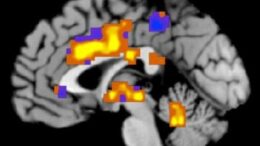

Οι μαγνητικές τομογραφίες «μετρούν» τον πόνο

Την υπογραφή του πόνου καταγράφουν οι λειτουργικές μαγνητικές τομογραφίες, αποδεικνύει…